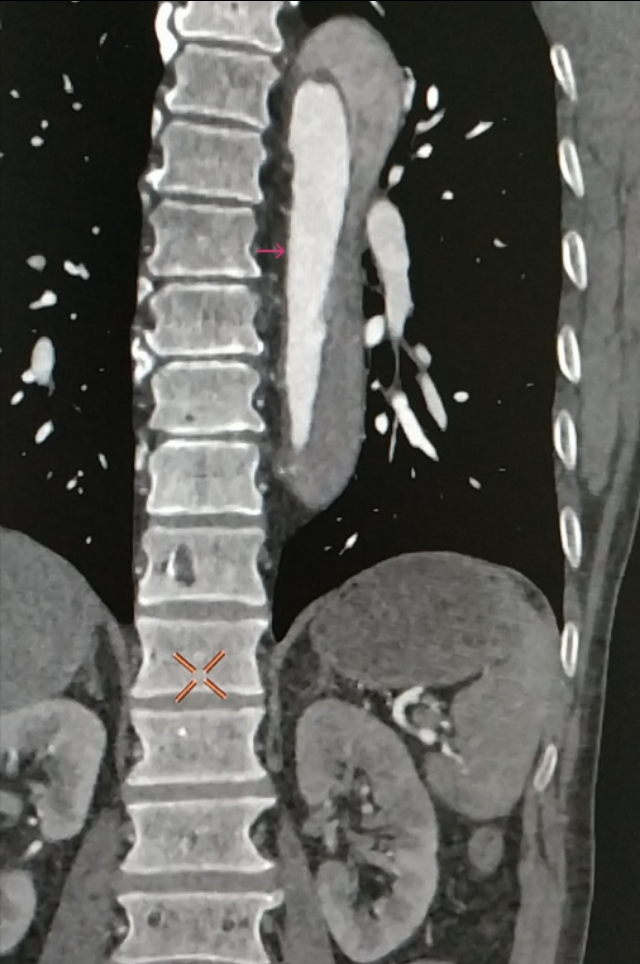

感觉不像,于是带着疑问,跟家属沟通好,我们给患者做了肺动脉和主动脉的全层CTA,发现是那个隐藏已久的杀手——主动脉夹层。而且,是全层撕裂,如下图。

这下疑团解开了,患者胸痛且低血压休克有了解释、没有低氧血症也有了解释,可D-二聚体高到了上限,这么离谱的数值竟然发生在一个主动脉夹层的病人身上,还是第一次见,这又产生了新的质疑:主动脉夹层的患者D-二聚体也会这么高?

咱们再聊聊主动脉夹层这个病。主动脉夹层是血管撕裂性疾病,指的是人体最大的血管主动脉内膜破裂,血流在经过破口的时候进入中膜,形成真假两腔,类似于双层水杯,类似于轮胎鼓包,这样的一种疾病。死亡风险极其高,多数病人有突发的胸痛,也可以各种症状出现,临床迷惑性极强。

因此,既然是血管内膜的破裂,由于血管的生理保护机制,血小板就会出现聚集进行止血,凝血系统也会被激活参与止血,形成血凝块,只是这种血凝块发生在我们的大血管上,跟我们的手磕破了发生的过程一样。而体内另一个系统——纤溶系统为了对抗凝血也会分解掉一部分血栓变成D-二聚体产生抗凝的效果,只是效果比较弱而已,于是,凝血与血栓分解就这样动态平衡着,直到某一方战胜另一方(出血、凝血、纤溶三者动态平衡相互制约)。